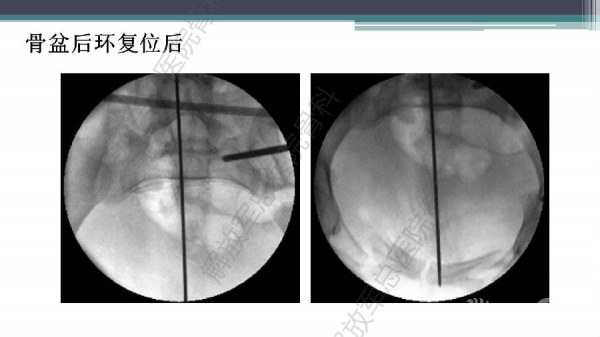

随着建筑和交通运输业的快速发展,合并骨盆、髋臼骨折多发伤、复合伤患者逐年增加,病死率和致残率都非常高。由于多发伤及复合伤、休克等往往不能在急性期对骨盆骨折进行确切复位及内固定,导致陈旧性骨盆骨折畸形愈合,从而产生一系列严重并发症,并且畸形矫正手术难度大、风险高、效果差。因此在抢救复苏后能不能尽早地、小切口甚至不切开、精确复位与固定骨盆骨折,防止陈旧性骨盆畸形愈合形成,成为广大骨科医生的挑战。解放军总医院创伤骨科在骨盆、髋臼骨折微创治疗方面做了一些工作,从微创理论探讨、到手术方法的改进,乃至钢板螺钉、微创复位器械等相继研发,形成了一系列的解决方案和配套内固定产品,为骨盆髋臼骨折的微创治疗奠定了基础。本幻灯则通过一例陈旧骨盆骨折畸形愈合的复杂治疗做引,通过介绍骨盆空间移位方式、透视特点、骨盆随意外架复位系统、复位原理以及1例典型病例的具体实施方案来综合、全面介绍我院微创骨盆髋臼骨折复位、固定新技术。